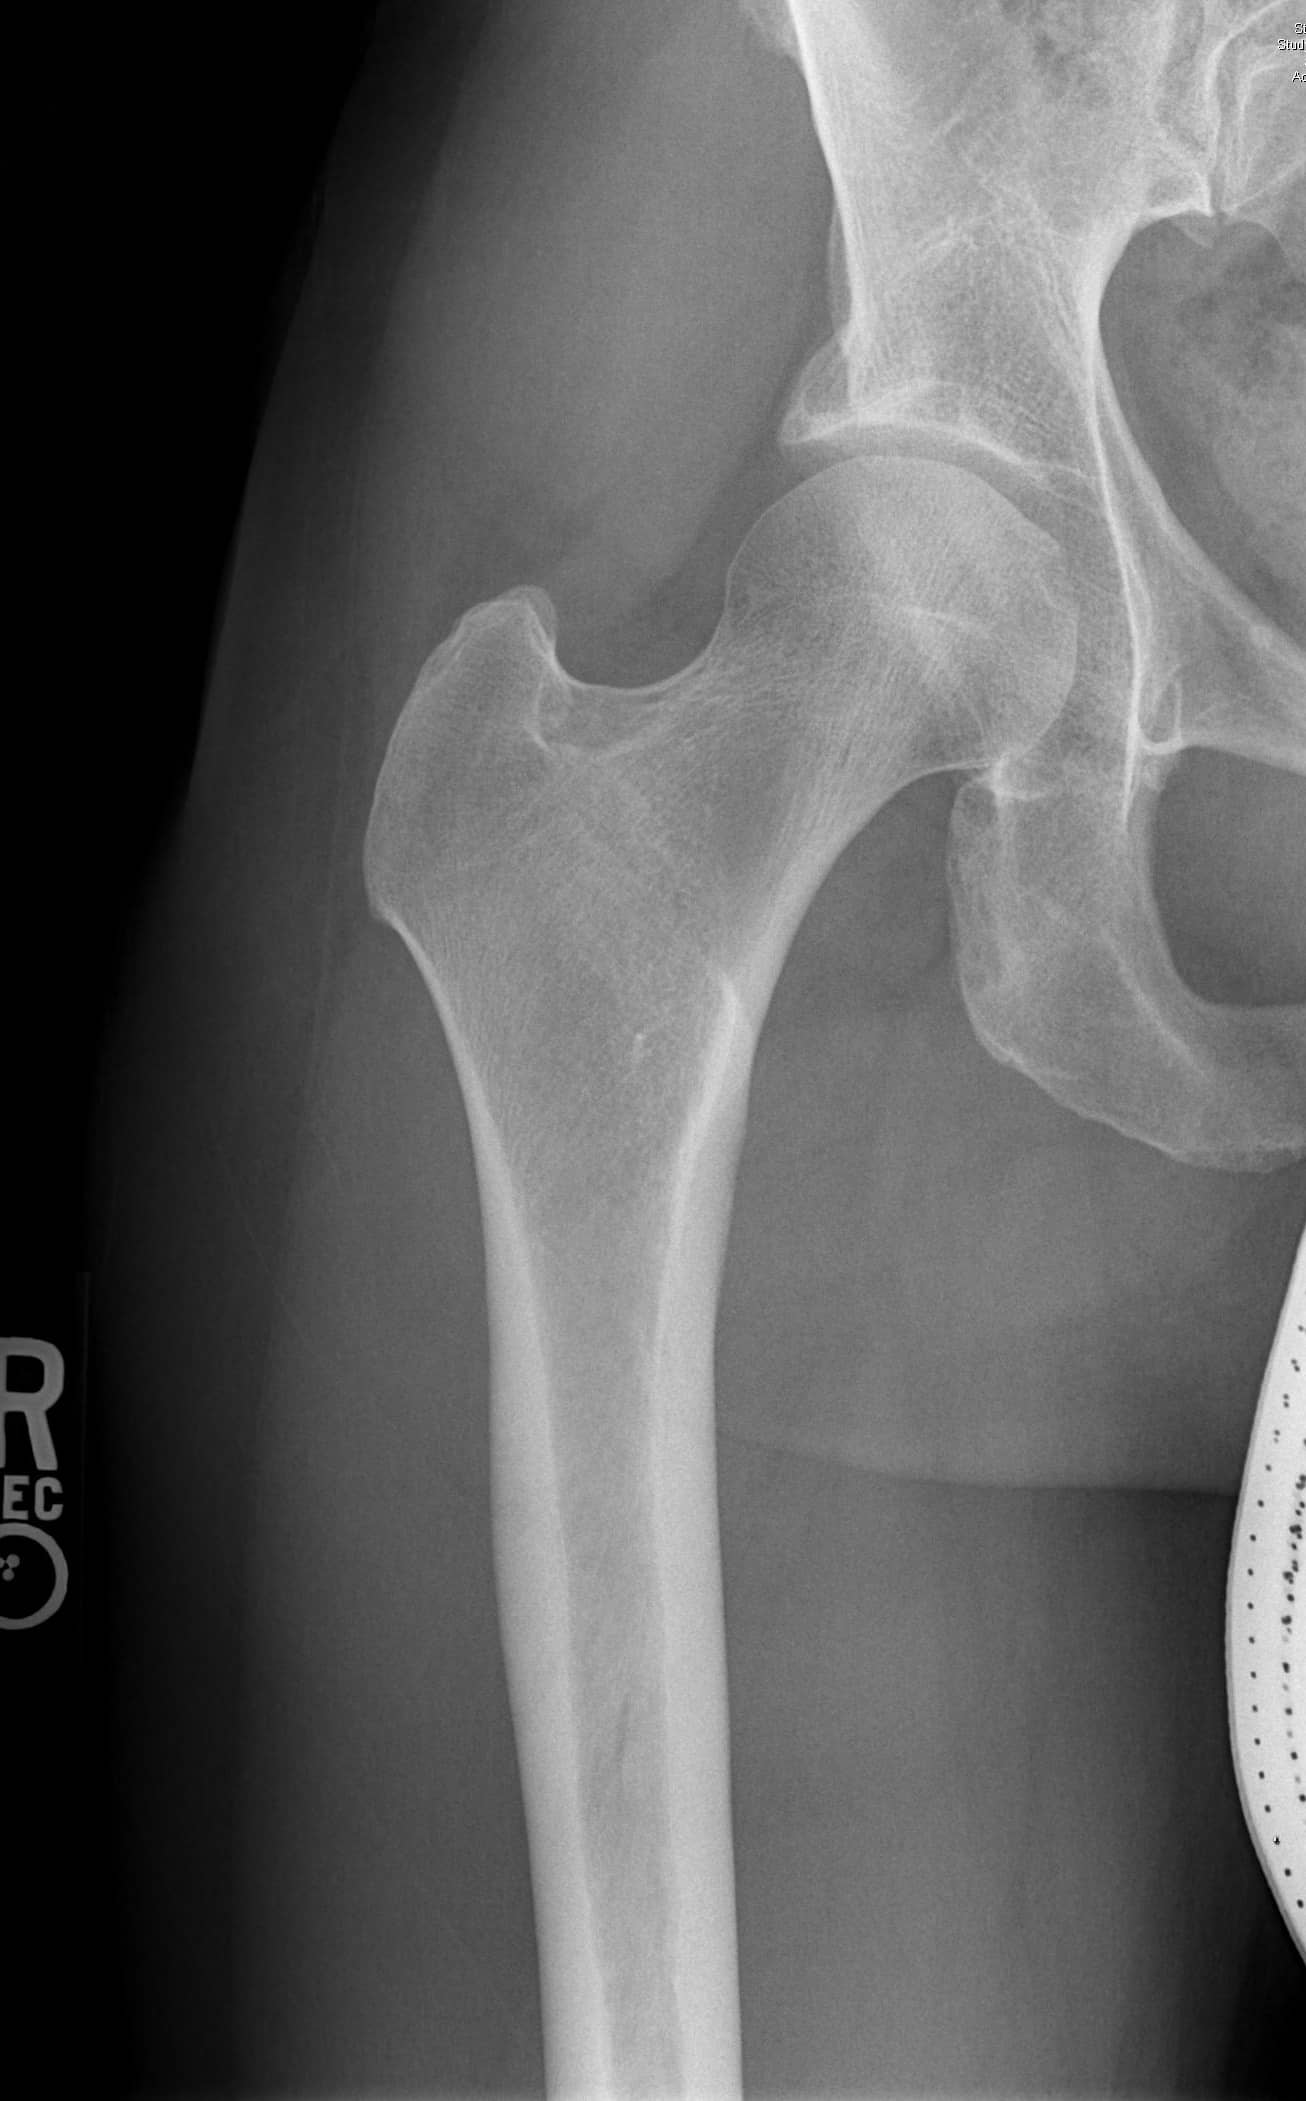

एक एपी श्रोणि दृश्य प्रभावित और अप्रभावित फेमोरा की तुलना की अनुमति देता है। यह सुनिश्चित करने के लिए समरूपता का आकलन करें कि एक सच्चा एपी दृश्य कैप्चर किया गया है। इसका आकलन यह जांचकर किया जा सकता है कि कोक्सीक्स सिम्फिसिस पबिस को ओवरलैप करता है, जिसमें दो संरचनाओं के बीच 2 सेमी से अधिक अलगाव नहीं होता है। संयुक्त स्थान में कमी और अपक्षयी परिवर्तनों के लिए संयुक्त का मूल्यांकन किया जाना चाहिए। अप्रभावित पक्ष के साथ एंटेरोलेटरल गर्दन समोच्च की तुलना करें। बेहतर गर्दन की शंकु की कमी सिर-गर्दन ऑफसेट को कम करने का संकेत देती है। एंटेरोसुपीरियर या पूर्ववर्ती सिर की सपाट या बढ़ी हुई त्रिज्या एक गोलाकार सिर को इंगित करती है। कई मापों का विश्लेषण किया जा सकता है:

- पार्श्व केंद्र एज कोण: ऊरु सिर के केंद्र से खींची गई एक ऊर्ध्वाधर रेखा द्वारा बनाया गया कोण और पार्श्व रिम से सिर के केंद्र तक खींची गई रेखा। 20 डिग्री से कम कोण डिस्प्लेसिया को इंगित करता है।

- एसिटैबुलर इंडेक्स: एसिटैबुलर छत या सॉर्सिल द्वारा बनाया गया कोण। 10 डिग्री से अधिक का कोण डिस्प्लेसिया को इंगित करता है।

- एसिटैबुलर संस्करण: एसिटेबुलर रिम के पूर्ववर्ती और पीछे के अनुमानों के साथ एंटेरोलेटरल एसिटेबुलर किनारे से रेखाओं का पता लगाता है। एक पूर्ववर्ती दीवार जो पीछे की दीवार ("पीछे की दीवार का संकेत") की तुलना में अधिक पार्श्व है, रेट्रोवर्सन को इंगित करती है। एक पूर्ववर्ती दीवार जो पीछे की दीवार ("क्रॉस-ओवर साइन") को पार करती है, पूर्ववर्ती रिम और सापेक्ष रेट्रोवर्सन पर बोनी अधिकता को इंगित करती है।